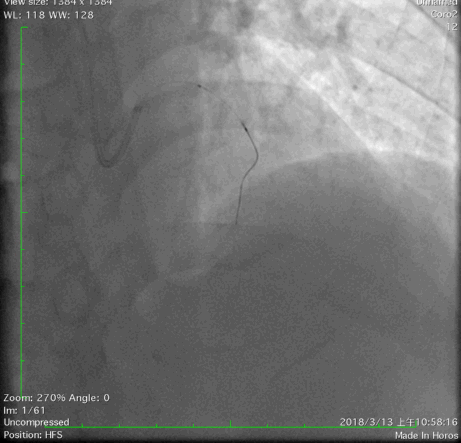

经右股动脉(8F),送EBU 3. 5指引导管指引导管至左冠开口。Sionblue导丝至LCX保护,Finecross 130到达LCX远端待命。Sionblue引导Corsair 135cm微导管进入LAD。近段纤维帽坚硬(伴钙化随后IVUS证实)尝试使用Gaia1st进入前次假腔,导丝升级Gaia 3rd谨慎前进入间隔支S1,推送corsair进入S1交换KDLC,Pilot 200导丝平行进入LAD真腔。Corsair交换Sionblue到LAD远端。IVUS证实全程真腔,闭塞段以纤维为主。植入支架完成血运重建。

Pilot200进入真腔

结果

IVUS影像提示导丝位于闭塞段斑块内,斑块以纤维斑块为主。